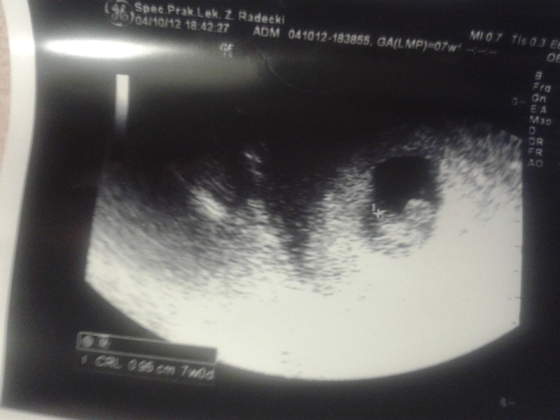

:-(. Dostalam recepte na zelazo bo hemoglobina u mnie kiepsciutka, poza tym straszne cisnienie 150/90

, wiec znow dostalam doodatkowy Dopegyt, a juz biore Isoptin, masakra ehh, do powtorzenia mam badanie moczu bo leukocyty wyszly, no i za 2 tygodnie USG z ocena plodu/genetyczne. To chyba tyle